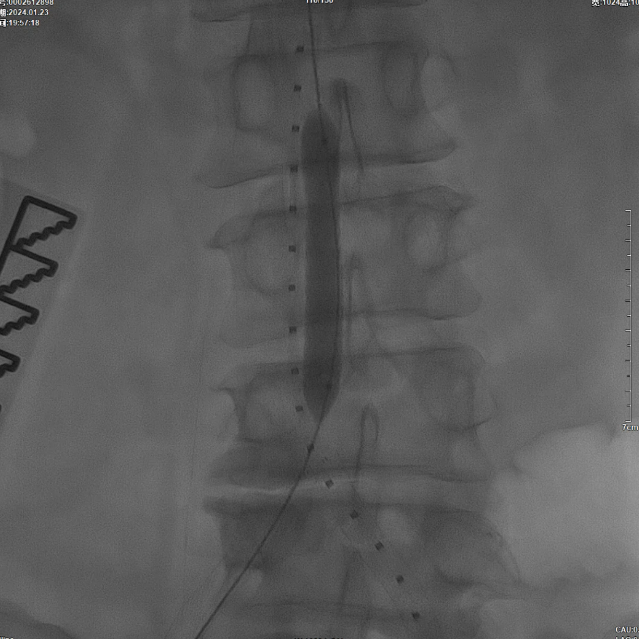

穿刺与造影

在超声引导下,成功完成双侧股总动脉穿刺。通过导管配合超滑导丝,顺利通过病变区域进入腹主动脉下段,造影明确腹主动脉下段及双侧髂动脉完全闭塞的病变范围与程度。

减容治疗

采用8F Rotarex导管对双侧髂动脉及腹主动脉下段进行减容处理。该器械对于陈旧性血栓具有良好的清除效果,且适用于支架内病变的治疗。减容治疗的主要目的在于获得理想的管腔空间,同时降低远端动脉栓塞的风险。